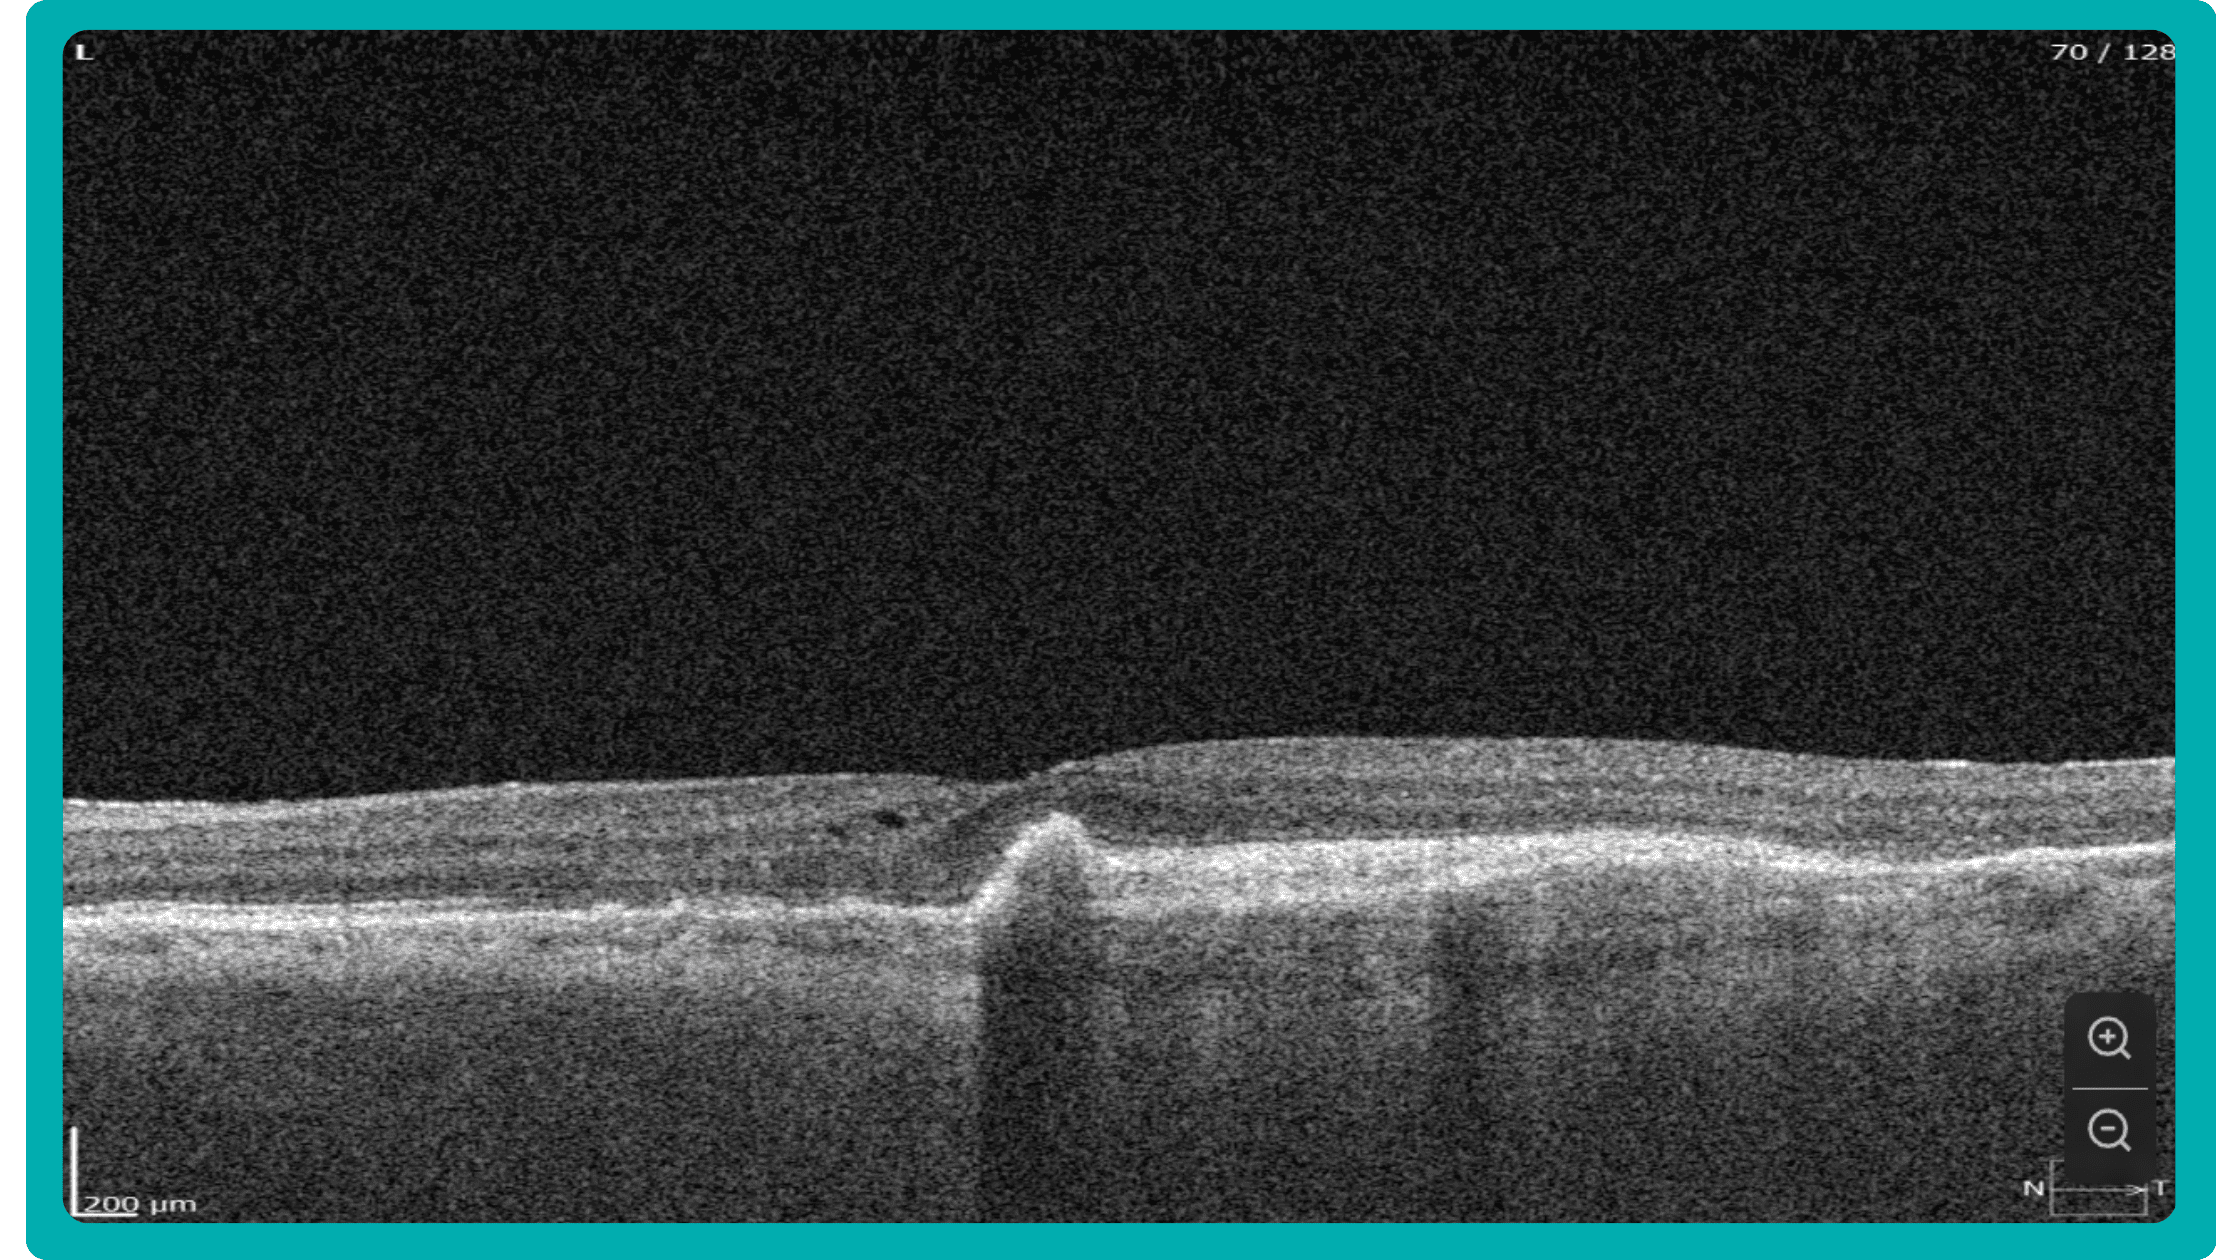

While retinal reports vary among OCT models, they typically include:- a foveally centered B-scan,

Firstly, acquired 2D image slices are presented individually. This allows for detailed examination, but navigating through numerous images can be cumbersome, particularly with large datasets.

Let’s explore how this applies to a clinical case, such as monitoring a patient with Wet AMD during follow-up visits.

Data demonstrates that OCT findings can reveal the onset or progression of neovascular AMD before a patient reports new symptoms or changes in visual acuity. In fact, OCT images are reported to have the best diagnostic accuracy in monitoring nAMD disease states. This underscores the importance of key OCT findings or biomarkers in personalizing anti-VEGF treatment, achieving disease control, and reducing monitoring burdens.

Central Retinal Thickness emerged as one of the earliest OCT biomarkers used as an outcome measure in clinical trials for nAMD.

However, due to confounding factors, CRT’s use in outcome-based assessments of nAMD varies. Thus, it is essential to evaluate additional morphological changes alongside retinal thickness and their relationships with functional outcomes.

Another finding that is correlated with a worsening VA due to the associated photoreceptor defects is any damage to the four outer retina layers, including the RPE, interdigitation zone (IZ), ellipsoid zone (EZ), and external limiting membrane band (ELM).

OCT is a valuable imaging tool for visualizing subretinal hyperreflective material (SHRM). It can automatically identify and quantify SHRM and fluid and pigment epithelial detachment to calculate the overall risk of worsening visual outcomes associated with SHRM.

Subsequent follow-up visits will then display the most relevant picture, highlighting the most pertinent biomarkers for tracking a particular pathology (wet AMD in our example) and comparing their volume, progression, or regression through visits.

Another helpful option is retinal layer segmentation, which focuses solely on the retinal layers of interest for the specific case.